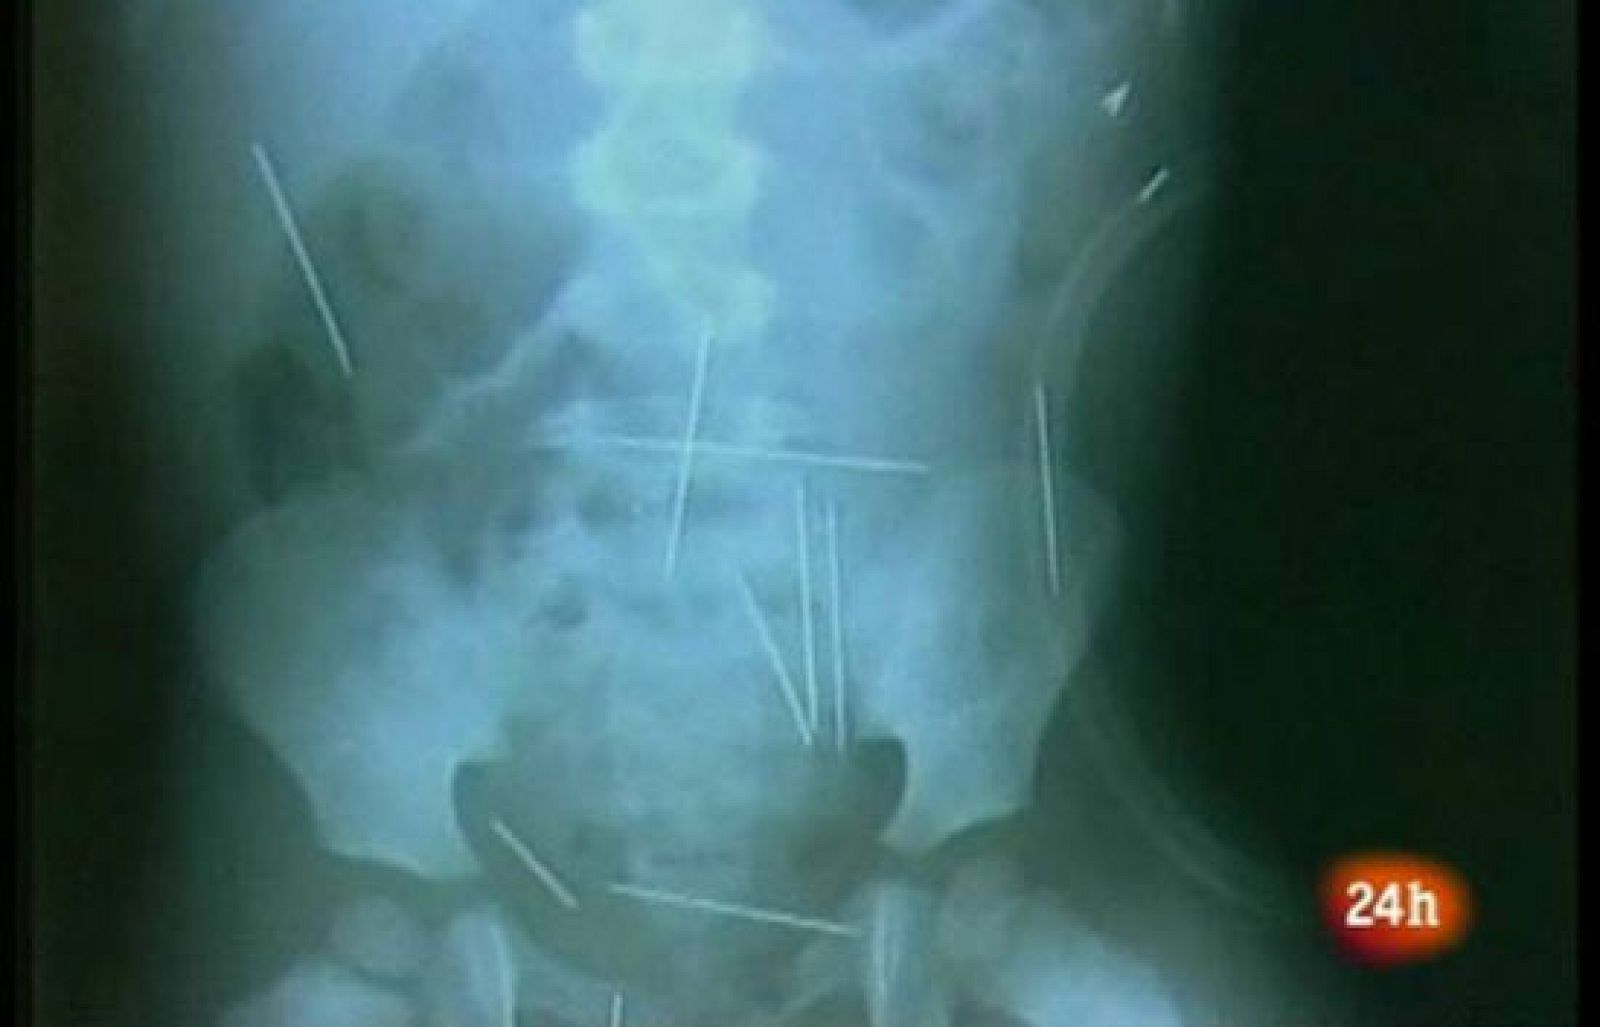

El niño con agujas en el cuerpo, víctima de un ritual

El menor comenzó a protestar de dolores de barriga la semana pasada y, cuando fue llevado al hospital, los médicos descubrieron las agujas al realizarle una radiografía.

El niño, que se encuentra con pronóstico grave, espera al inicio de la operación en la que se le van a extraer las agujas, que incluso le han perforado un pulmón.

Tras someterle a nuevos exámenes, se descubrió que tenía 40 objetos metálicos clavados en diferentes partes del cuerpo, desde el pecho hasta las piernas.

Inicialmente, se calculó que el número de agujas ascendía a cincuenta, pero hoy los médicos rebajaron sus estimaciones, a la vez que estudiaban la mejor manera de realizar la intervención médica.